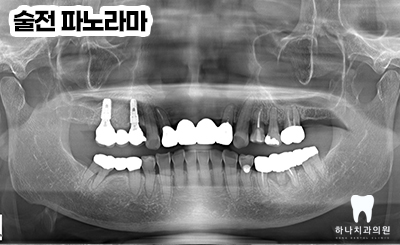

위 환.자분은 70대 여성분으로

새로 제작한지 얼마 되지 않은

앞니 보철물이 부러지고 덜렁거리신다며

내원해 주셨습니다.

본인의 원래 위, 아래 치아 사이의

수직적 높이인 교합고경이

낮은 상태임에도 무리하게 크고 긴

앞니 보철이 제작되어 보철이 깨지고

지대치인 양쪽 측절치가 심하게

흔들리고 있는 상태였는데요.

사진에서 보이는 바와 같이

이를 꽉 문 상태에서 아래 앞니가 하나도

보이지 않을 정도의 과한 수직 교합을

보이고 있었는데

그 이유로 부족한 어금니의 높이 때문에

위쪽 앞니가 들어갈 공간이 부족하여

보철의 깨짐과 지대치의 동요도를 보인다고

판단하였습니다.

따라서 양쪽 어금니의 높이를 높여

충분한 수직적 교합 거상 후

생리적으로 안정적인 크기인

앞니 임플란트 보철까지

진행하기로 하였습니다.

양쪽 아래 어금니의 임플란트 보철을

만들면서 환.자가 가지고 있는

수직적 높이를 올려 앞니의 공간을

부여할 수 있도록 디자인하였는데요.